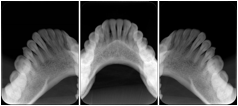

2 Occlusal Vertical Maxilla A Dental Image Layout

DL-C001A

Reference: DL-C001-U1L0

Reference: DL-C001-U2L0

00

Occlusal

18, 17, 16, 15, 14, 13, 12, 11, 13, 12, 11

01

21, 22, 23, 24, 25, 26,27, 28

2 Occlusal Vertical Mandible A Dental Image Layout

DL-C002A

Reference: DL-C002-U0L1

Reference: DL-C002A-U0L2

10

48, 48, 47, 46, 45, 44, 43, 42, 41

11

31, 32, 33, 34, 35, 36, 37, 38

2 Occlusal Horizontal Maxilla A Dental Image Layout

DL-C003A

Reference: DL-C003-U1L0

Reference: DL-C003-U2L0

18, 17, 16, 15, 14, 13, 12, 11, 13, 12, 11, 21, 22, 23, 24, 25, 26,27, 28

2 Occlusal Horizontal Mandible A Dental Image Layout

DL-C004A

Reference: DL-C004-U0L1

Reference: DL-C004-U0L2

48, 48, 47, 46, 45, 44, 43, 42, 41, 31, 32, 33, 34, 35, 36, 37, 38